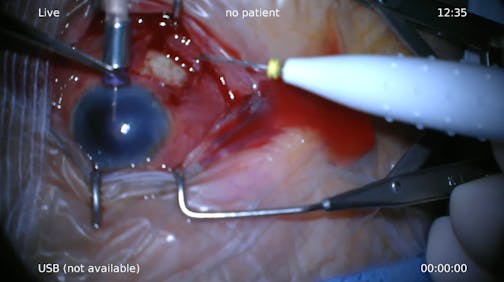

Trauma

Grazia Pertile, MD